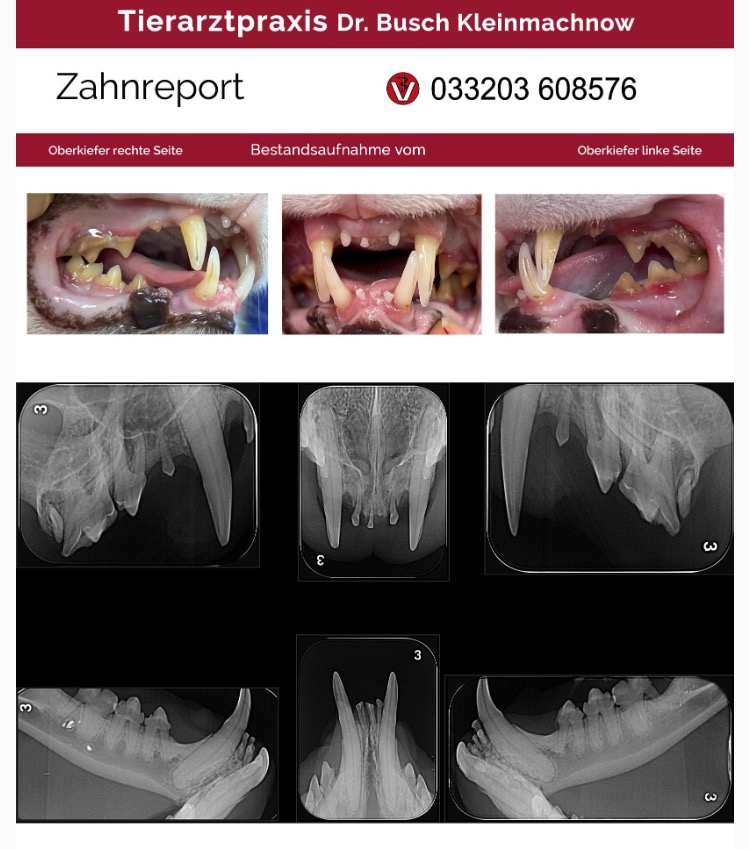

Doch bei der tierärztlichen Kontrolle dann der Schock - seine Zähne waren fast alle nahezu krank oder abgebrochen. Was musste der arme Kerl alles schon erlebt haben…?

Die komplette Zahn-OP hat 2.500 Euro gekostet. Bito hat nun nur noch 4 Fangzähne, aber er kommt damit super zurecht.